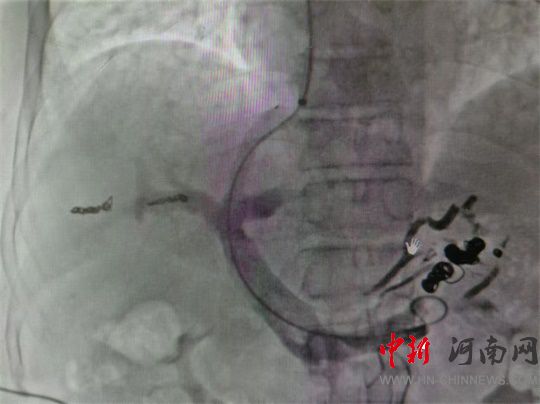

經(jīng)家屬同意

麻恒翔為李先生開展

DSA下門靜脈造影

經(jīng)頸靜脈肝內(nèi)門體分流術(shù)

胃冠狀靜脈栓塞術(shù)

通過右側(cè)頸動(dòng)脈穿刺

引入動(dòng)脈鞘、導(dǎo)管

造影顯示

胃冠狀靜脈

血管極度紊亂

經(jīng)導(dǎo)管注入血管膠

及不同直徑

栓塞彈簧圈

封堵破裂血管

(導(dǎo)管開通分流道)

隨后串聯(lián)

門靜脈血管

與肝靜脈血管

架橋成功

手術(shù)順利

僅留下2mm開口